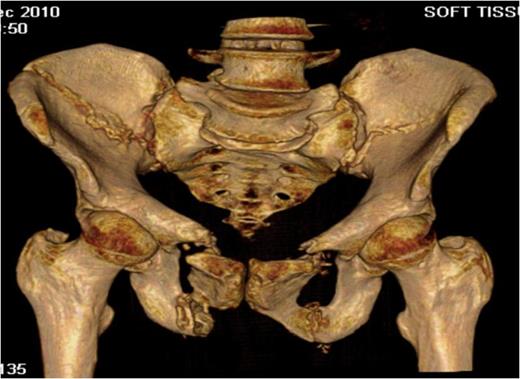

Inlet radiograph at 16 months post surgery demonstrating solid fixation and bony healing

Post-operative recovery was uneventful. Bone and soft tissue biopsies showed no abnormalities. She was kept non weight bearing for 12 weeks. Subsequent dual energy X-ray absorptiometry scanning revealed mild osteopenia for which she is being managed medically. She began full weight bearing at 3 months post surgery. Final follow-up at 16 months demonstrated that the fractures had healed, and the patient was pain free and mobilising unaided (Fig. 3 & 4).